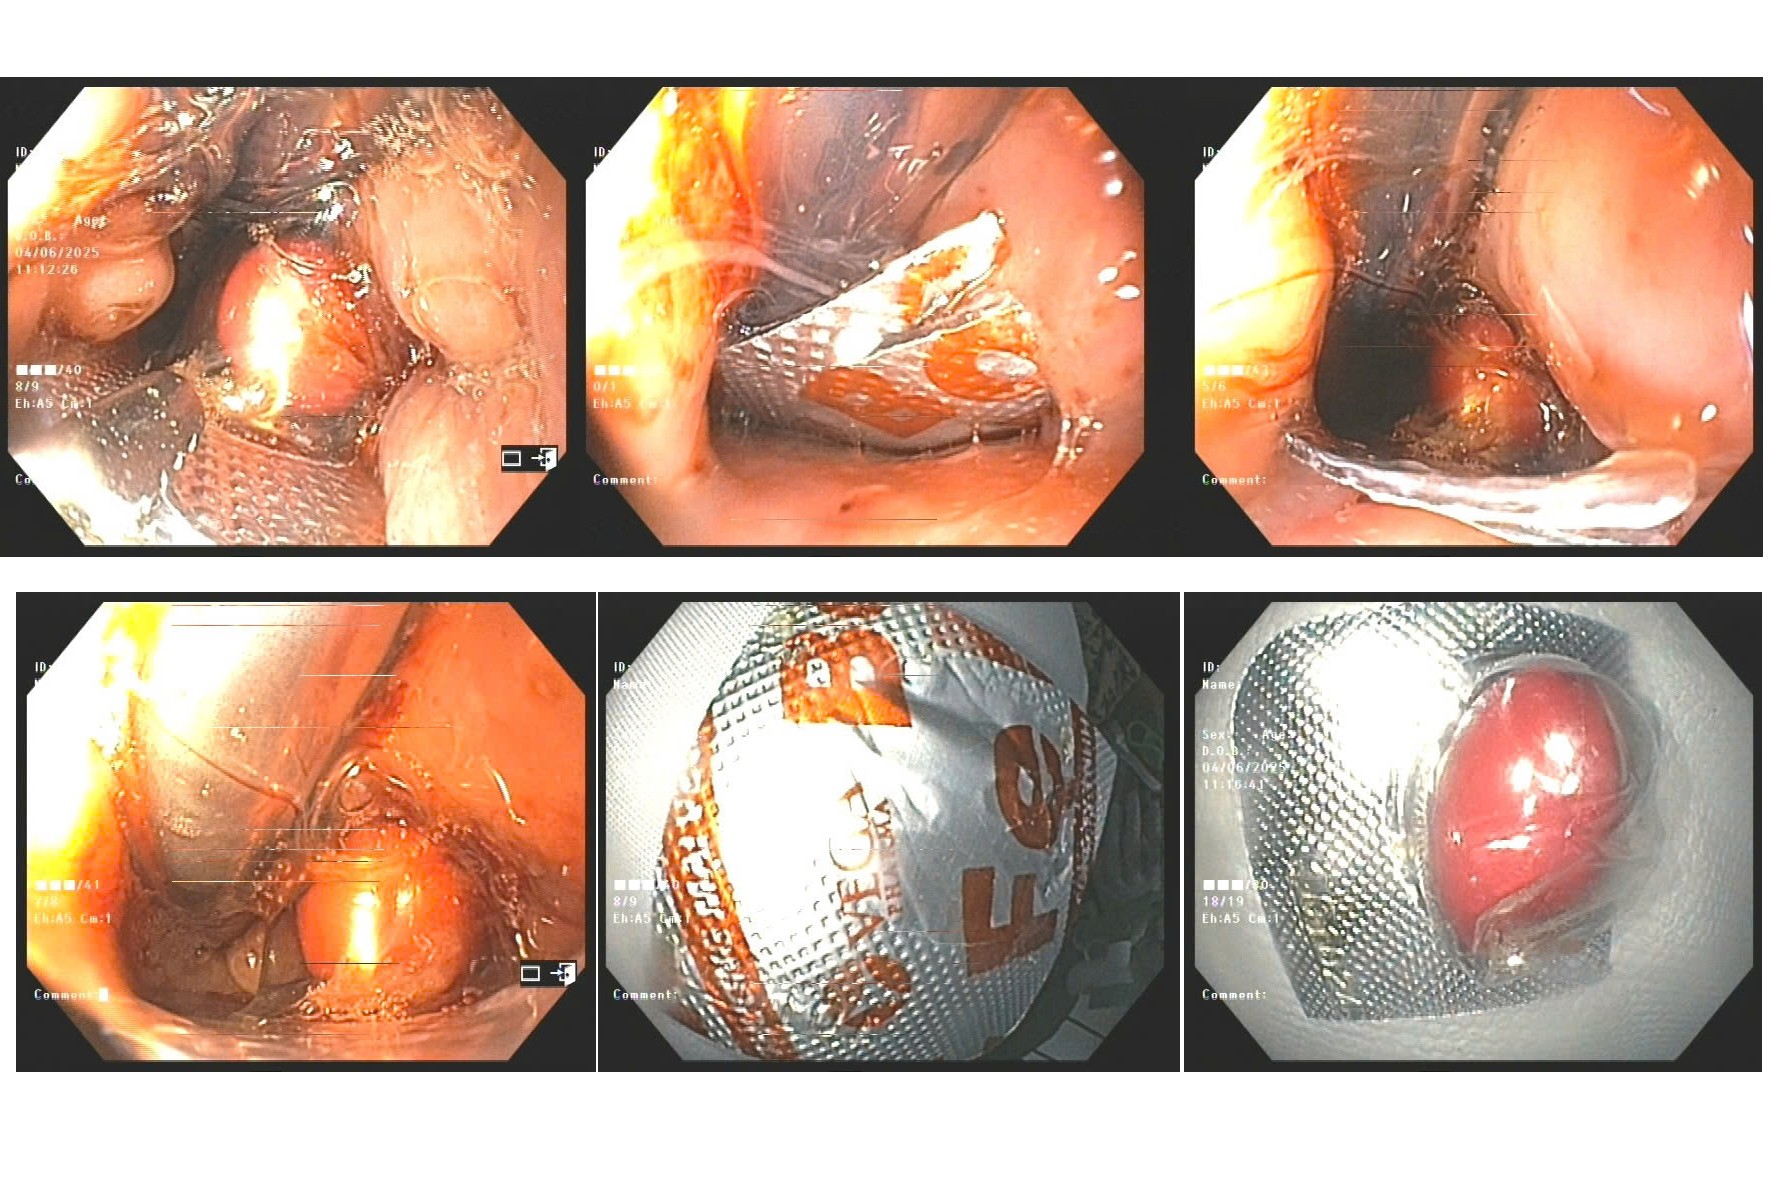

Ngay khi tiếp nhận tại phòng khám Tai Mũi Họng vào ngày 9 tháng 6, bệnh nhân T.T.H. đã được Bác sĩ Lưu Thị Ngọc Yến và ekip y tế khẩn trương thăm khám lâm sàng. Qua nội soi tai mũi họng, các bác sĩ phát hiện một viên thuốc còn nguyên vỏ bọc, dạng nang, đã bị mắc kẹt tại vùng miệng thực quản. Điều đáng lo ngại là cạnh sắc của vỏ nang đã găm trực tiếp vào niêm mạc thực quản, gây đau đớn dữ dội cho bệnh nhân. Nhận định đây là một dị vật sắc nhọn có nguy cơ cao gây tổn thương thực quản nghiêm trọng nếu không được xử lý kịp thời và đúng cách.

Ngay lập tức, vào khoảng 10 giờ 20 phút, phòng Tai Mũi Họng đã liên hệ khoa Nội Soi Tiêu Hóa để tiến hành nội soi dạ dày gây mê cho bệnh nhân. Ca nội soi đã diễn ra thành công, dị vật được gắp ra an toàn. Đó là một viên thuốc còn nguyên lớp vỏ gelatin. Phần cạnh cứng và sắc của vỏ thuốc đã gây ra một vết xước nhỏ trên niêm mạc thực quản.

| Các bác sỹ đang tiến hành xử lý lấy vỏ viên thuốc ra (Ảnh: Thụy Miên) |

May mắn thay, sau khi kiểm tra nội soi hậu thủ thuật, các bác sĩ không ghi nhận tổn thương sâu hơn, không có bất kỳ tai biến chảy máu hay thủng thực quản nào xảy ra. Bệnh nhân T.T.H. sau đó đã được kê toa thuốc bảo vệ niêm mạc, kháng viêm nhẹ và được hướng dẫn theo dõi tại nhà. Tình trạng sức khỏe của bà hiện đã ổn định và dự kiến có thể sinh hoạt ăn uống trở lại bình thường sau 1-2 ngày.

| Viên thuốc mắc kẹt tại vùng miệng thực quản (Ảnh. Mộc Miên) |